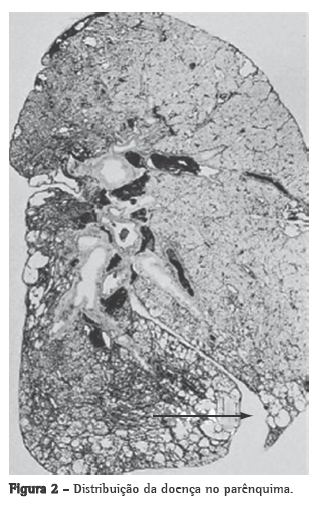

O diagnóstico histológico de PIU baseia-se em uma série de características de distribuição da doença, definindo um padrão histopatológico.(23) O tamanho do segmento de tecido pulmonar tem relação com a profundidade da amostra no parênquima pulmonar. A biópsia pulmonar deve apresentar a região periférica, subpleural, como a região mais central ou medular do pulmão. Outra recomendação é obter a amostra dessa transição entre a região nitidamente doente visualizada na TCAR e a região de aspecto aparentemente normal.(24) A TCAR permite uma ótima avaliação de todo o parênquima pulmonar, sendo rotina da avaliação inicial das doenças pulmonares intersticiais.(25) Hoje, utiliza-se a TCAR como exame de rotina no pré-operatório de qualquer biópsia cirúrgica do pulmão (Figura 1).

A TCAR permite, com razoável precisão, selecionar os locais ideais para a biópsia com estágios distintos da doença no parênquima pulmonar.